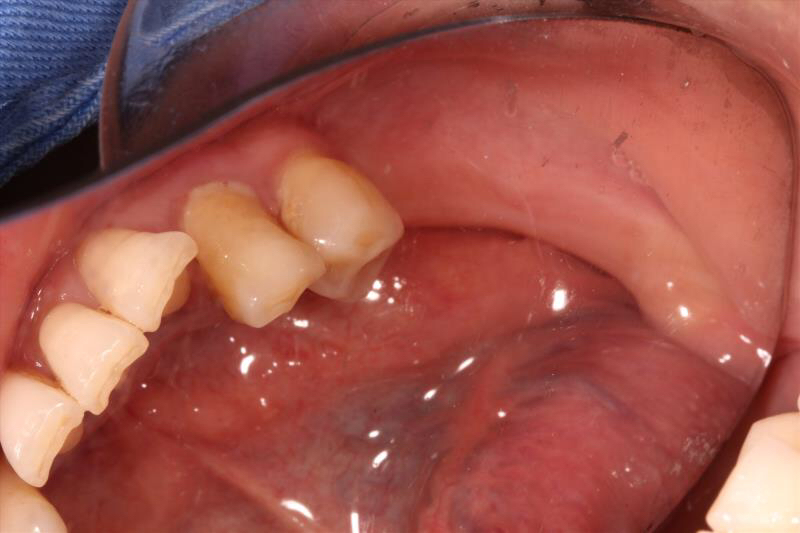

患者中年女性,左下5、6、7缺失多年,牙槽骨吸收较多,CBCT可见牙槽骨高度不足,距离下颌神经管比较近,所以为这位患者选择了短植体进行种植,术中植骨盖膜,历时7个月戴上了牙齿,患者使用满意。